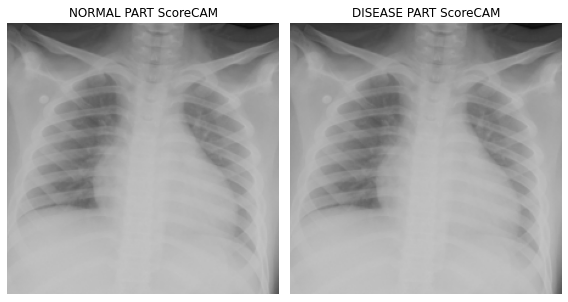

fig, (ax1,ax2) = plt.subplots(1,2)

dls.train.decode((x,))[0].squeeze().show(ax=ax1)

ax1.imshow(-cam_scorecam.squeeze(),alpha=0.5,extent=(0,224,224,0),interpolation='bilinear',cmap='cool')

ax1.set_title("NORMAL PART ScoreCAM")

#

dls.train.decode((x,))[0].squeeze().show(ax=ax2)

ax2.imshow(cam_scorecam.squeeze(),alpha=0.5,extent=(0,224,224,0),interpolation='bilinear',cmap='cool')

ax2.set_title("DISEASE PART ScoreCAM")

fig.set_figwidth(8)

fig.set_figheight(8)

fig.tight_layout()